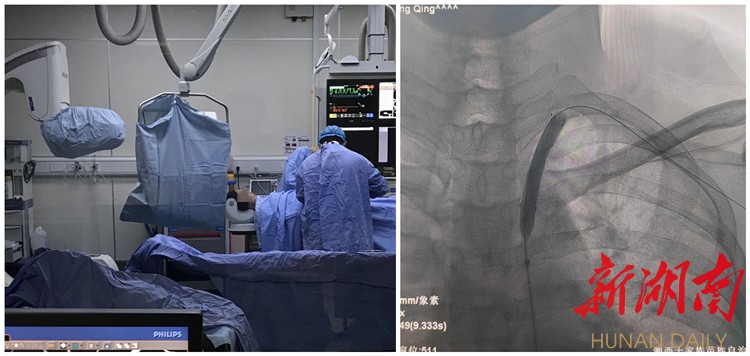

新湖南客户端3月25日讯(通讯员 田志 陆山)近日,湘西土家族苗族自治州人民医院神经介入建设中心,成功为一名左侧锁骨下动脉盗血患者,实施了动脉近端狭窄成形术,术后患者狭窄血管恢复通畅,左椎恢复正向血流,症状完全缓解。

54岁的黄先生因“反复头晕伴双上肢麻木不适”来到神经外二科就诊,经过全脑血管造影术检查后发现,患者“左侧锁骨下动脉近端狭窄引起盗血”,因动脉血流反转诱发头晕,需行动脉近端狭窄介入治疗。

在介入科的密切配合下,神经外二科团队在局麻下为黄先生实施左侧锁骨下动脉近端狭窄支架成形术,术中支架与血管壁贴合良好,对位准确无移位,左侧椎动脉血流正向,手术顺利完成。

“如采用常规内科治疗,无法根治头晕。”据神经外二科主任朱英杰介绍:但经血管介入输送球囊导管至锁骨下动脉狭窄处,扩张球囊重建动脉管腔,植入支架防止弹性回缩,可治愈狭窄的血管,且具有不开刀、创伤小、手术时间短、并发症少、患者恢复快等优势。